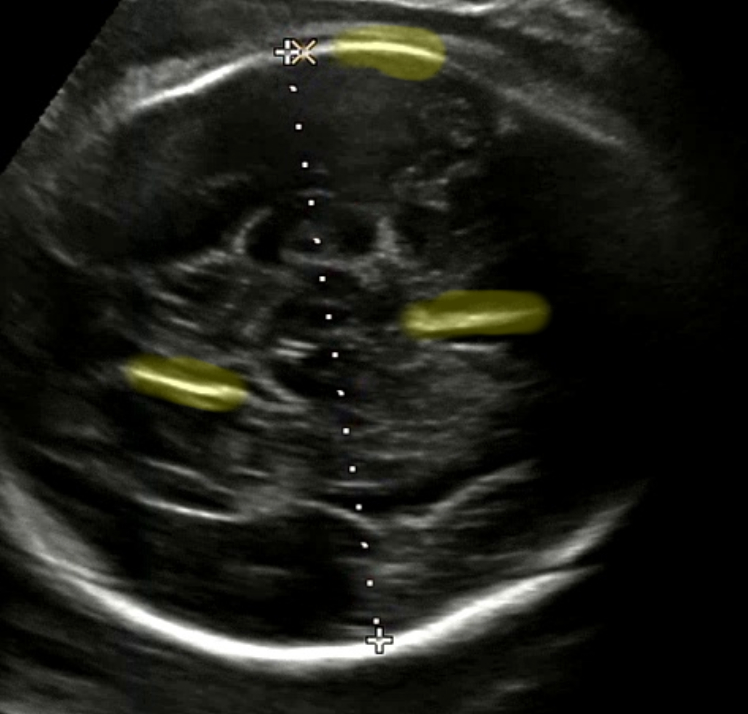

기존에 두개골을 찾는 방법은 아래와 같다. 문제는 초음파 내 원형을 찾을 때 HoughCircles 함수를 사용한다. 그러나 초음파 영상은 해상도가 상대적으로 낮고 영상 내에 정말 다양한 노이즈가 많다. 점선 원을 찾는 과정에서 원이 보이지 않으면 원의 크기를 키워나갈 때 내가 하드 코딩한 값으로 찾게 된다. 당장 내가 테스트한 이미지는 잘 인식이 되더라도 다른 이미지는 그것을 보장할 수 없다. 아래 예시가 그러하다. (아래 사진이 아닌) 다른 초음파 이미지에서는 배율이 축소된 영상인지 태아의 두개골이 작은 원이었다. 그래서 그 원을 인식하기 위해 값을 보정하면 아래 사진은 제대로 두개골이 인식이 되지 않는다. 기존 방법은 이미지 편차가 크다.

점선 패턴을 인식하는 방법을 선택했다. 점선 패턴은 BPD 를 측정할 때 모든 영상에 출력된다. 그리고 우리는 개발자이기 때문에 의사의 판단을 넘어서는 행위를 하면 안 된다고 생각했다. 그래서 점선 패턴을 인식하고 같은 선상에 있는 점들을 찾아냈다. 그리고 찾아낸 점들 중 가장 먼 좌표 간 거리를 계산하여 픽셀 거리를 획득했다.